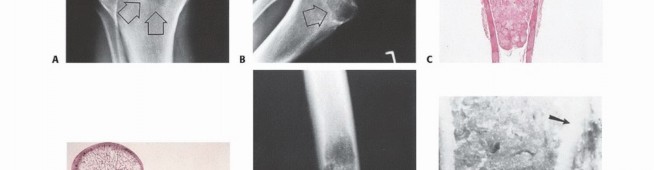

Enneking also established a robust staging system for benign osseous lesions based on clinical presentation and radiographic behavior:

* Stage 1 (Latent): Asymptomatic, discovered incidentally. Static growth or spontaneous healing. Thick, well-defined reactive sclerotic rim. Treated with observation or simple curettage (e.g., Non-ossifying fibroma).

* Stage 2 (Active): Progressive growth, mild symptoms, but contained within natural cortical barriers. Treated with extended curettage and burr drilling (e.g., Aneurysmal bone cyst).

* Stage 3 (Aggressive): Rapid growth, symptomatic, destroys cortical bone, and extends into soft tissue. Minimal to no reactive bone rim. Requires aggressive extended curettage with local adjuvants (liquid nitrogen, phenol, argon beam) or wide en bloc resection (e.g., Giant cell tumor of bone).

Radiographic and Advanced Imaging Modalities

- Plain Radiography: The cornerstone of initial evaluation. It accurately predicts the diagnosis in over 80% of extremity bone tumors. It defines the lesion's location, zone of transition (narrow/sclerotic = benign/slow; wide/permeative = malignant/aggressive), cortical destruction, and periosteal reactions (Codman triangle, onion-skinning, sunburst pattern).

- Computed Tomography (CT): The modality of choice for assessing fine osseous detail, cortical integrity, and matrix mineralization. Thin-slice (≤1 mm) helical CT allows for precise 3D reconstructions. Intravenous contrast is essential to delineate the relationship of the soft tissue mass to major vascular bundles. Chest CT is mandatory for staging to rule out pulmonary metastases.

- Magnetic Resonance Imaging (MRI): The gold standard for evaluating the local extent of the tumor. It accurately defines the intramedullary extent (allowing calculation of bone resection levels), soft tissue extension, joint involvement, and the presence of skip metastases. T1-weighted images best define marrow replacement; T2-weighted and STIR sequences highlight peritumoral edema and the soft tissue mass. Contrast enhancement differentiates cystic from solid components and clarifies neurovascular proximity.